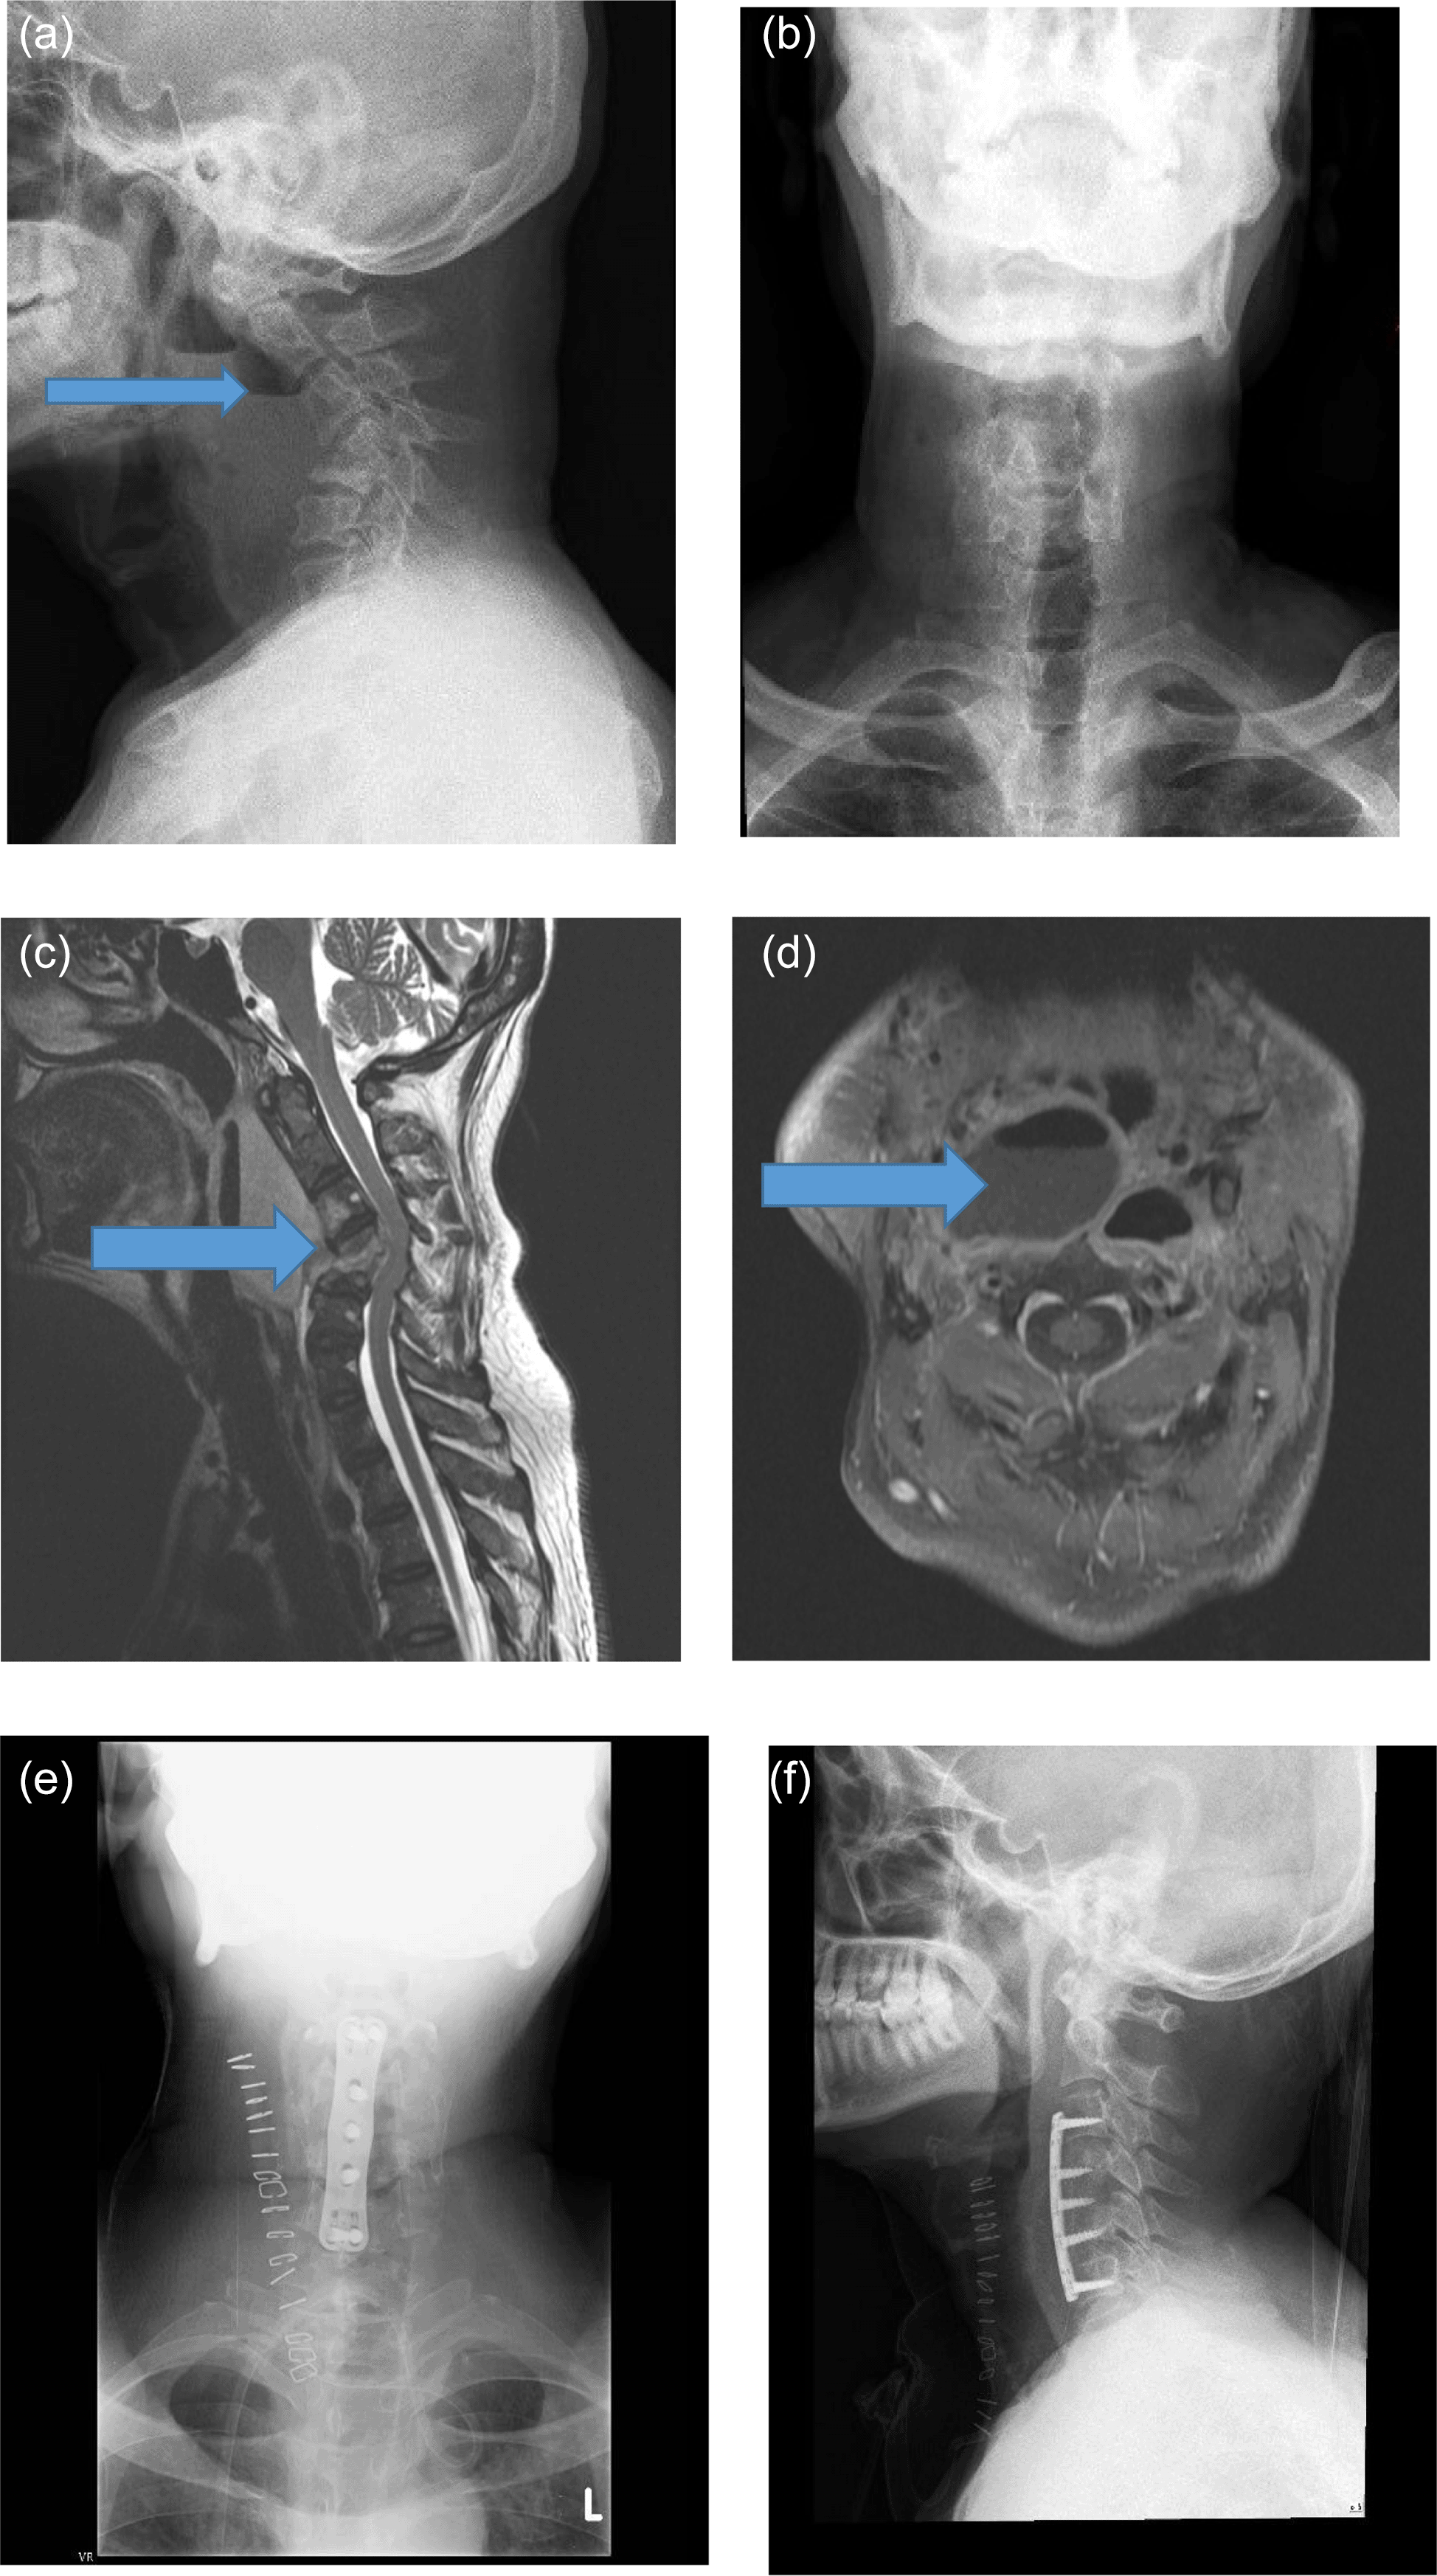

In an X-ray of the cervical spine, we noted increased prevertebral soft tissue shadow and erosion of vertebral end plates at C4-5 level with gross kyphosis. Air-fluid levels were also seen in the prevertebral soft tissue shadow (Figure 2a and b).

MRI of the cervical spine confirmed spondylodiscitis of C4-C5 with cord compression. Multiple collections in parapharyngeal space communicating with the pre-vertebral space were also seen along with air-fluid levels (Figure 2c and d)

He underwent anterior cervical decompression, by C5 corpectomy and fusion (Figure 2e and f). A distinct foul-smelling odour was noted intra-operatively and around 100 ml of pus was drained. The C4 and C5 vertebrae were completely destroyed with surrounding caseous material. Pus was sent for aerobic and anaerobic cultures and the caseating tissue was sent for histopathology. Patient tolerated the procedure well.